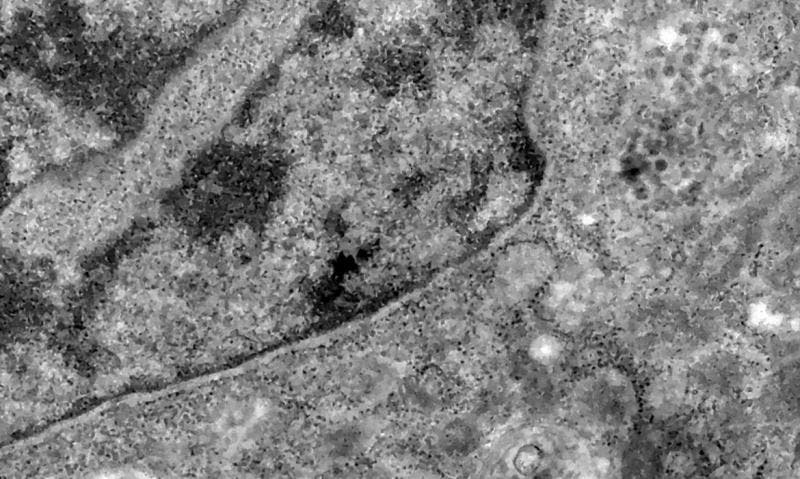

A variante Ômicron foi detectada pelo Instituto Nacional de Doenças Transmissíveis da África do Sul (NICD) em novembro de 2021. Segundo a Organização Mundial de Saúde (OMS), a Ômicron é altamente transmissível e com grande número de mutações.